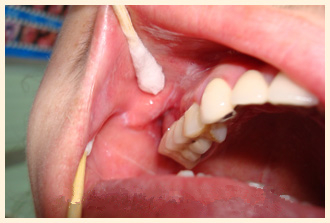

李先生,一名退休公务员,患口腔扁平苔藓多年, 唇部内侧黏膜常呈白色的圆或椭圆形斑块,表面可见白色网状损害硬,常... 【详细】

经薛主任指导用药三个月后,2012年6月复查白纹已不明显,7月开始减药至10月复查病灶白纹己完全消失。从2012年10月... 【详细】